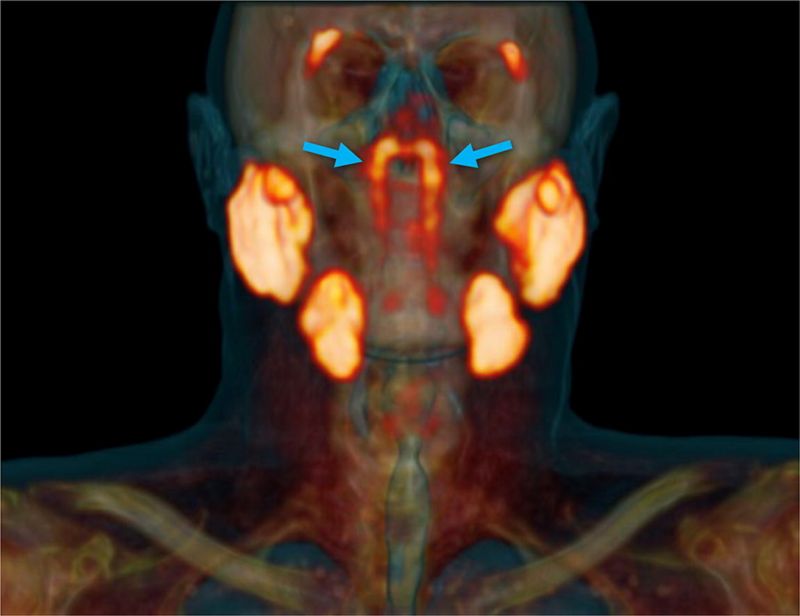

Олон зуун жилийн турш хүний бие организмын бүтцийг нэгд нэгэнгүй судалсан гэж үзэж байсан бол эрдэмтэд ийм эрхтэн байдаг талаар өнөөг хүртэл мэдээгүй байна. Түрүү булчирхайн хорт хавдартай өвчтөнд хамгийн сүүлийн үеийн PSMA PET/CT аппаратын тусламжтай үзлэг хийх үеэр энэхүү нээлтийг огт санамсаргүйгээр хийсэн байна.

Оношилгооны эл төхөөрөмжөөр авсан томограф зураг дээр залгиурын хойд хэсэгт нэгэн зүйлийг илрүүлжээ.

Харин эрдэмтдийн гайхшралыг төрүүлээд буй дөрөв дэх бүлэг шүлсний булчирхай хэмжээгээр том бөгөөд хамрын хойд, тагнайн дээд хэсэгт буюу тархины голд байрладаг байна.

Гуурсан булчирхай PSMA PET/CT аппаратын тусламжтай үзлэгт орсон 100 өвчтөнд бүгдэд нь илэрсэн байна. Түүнчлэн, эрэгтэй, эмэгтэй хүний цогцост хийсэн задлан шинжилгээгээр мөн энэ нээлт батлагджээ.